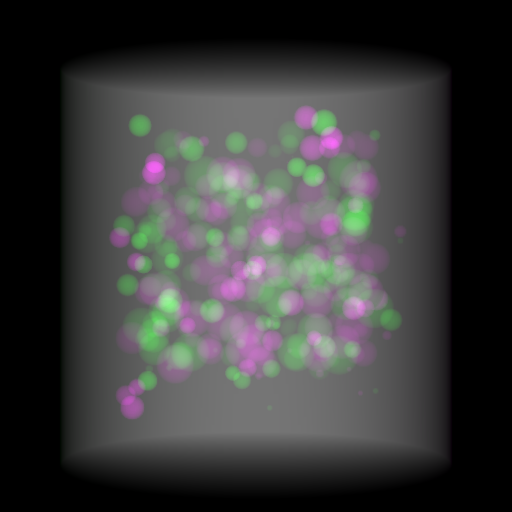

Refer to caption

(a) Orthogonal 0superscript00^{\circ}

(b) Perspective 0superscript00^{\circ}

(c) Perspective deformation ((b)-(a))

(d) Perspective 180superscript180180^{\circ}

(e) Difference of Perspective 0superscript00^{\circ} and 180superscript180180^{\circ}

(f) RGB 0superscript00^{\circ} and 180superscript180180^{\circ}

Figure 6: An example for perspective deformation learning from dual complementary views: (a) the orthogonal projection of the 3D bead phantom from the 0superscript00^{\circ} view; (b) the perspective projection from the 0superscript00^{\circ} view; (c) the difference image between (b) and (a); (d) the perspective projection from the 180superscript180180^{\circ} view; (e) the difference image between (d) and (b); (f) the RGB stack of the 0superscript00^{\circ} and 180superscript180180^{\circ} perspective projection images, where the magenta and green areas correspond to the positive (bright) and negative (dark) areas in (e). The intensity range [0, 11] is converted to [0, 255] for visualization.

Note that when and only when z=0𝑧0z=0, which is m=m=1superscript𝑚𝑚1m^{\prime}=m=1, d180subscript𝑑superscript180d_{180^{\circ}} and dPDsubscript𝑑PDd_{\text{PD}} both equal to 0. This provides a practical way to observe which structures suffer from perspective deformation by assessing deviations between the two complementary views.

The orthogonal and perspective projection images of the same 3D bead phantom in a complementary view setting are displayed in Fig. 6. Fig. 6(c) shows the perspective deformation, which is the difference between the perspective projection (Fig. 6(b)) and the orthogonal projection (Fig. 6(a)) from the 0superscript00^{\circ} view. Fig. 6(c) clearly demonstrates that the magnitude of perspective deformation increases from the center outwards radially. The 180superscript180180^{\circ} perspective projection image is displayed in Fig. 6(d) and its difference with respect to the 0superscript00^{\circ} perspective projection is displayed in Fig. 6(e). Fig. 6(e) is similar to Fig. 6(c) in bead areas, which illustrates that the deviation between two complementary views has strong correlation to perspective deformation. To integrate such dual-view information, like Fig. 5(d), we convert the perspective projections images from the 0superscript00^{\circ} and 180superscript180180^{\circ} views to a 3-channel RGB image in Fig. 6(f). The red and blue channels use images from the 0superscript00^{\circ} view, while the green channel uses images from the 180superscript180180^{\circ} view. In the RGB images, the color reveals the intensity difference between the 0superscript00^{\circ} and 180superscript180180^{\circ} perspective projection images. Grey areas contain close intensity values from both views. Instead, magenta and green areas indicate larger intensity values from the 0superscript00^{\circ} and 180superscript180180^{\circ} views respectively, where perspective deformation correction is necessary. They correspond to the positive (bright) and negative (dark) areas in the difference image in Fig. 6(e). In Fig. 6(f), the magenta beads and their corresponding green beads are located close to each other, which allows a network with limited receptive field size to capture bead-to-bead (point-to-point) dependency.